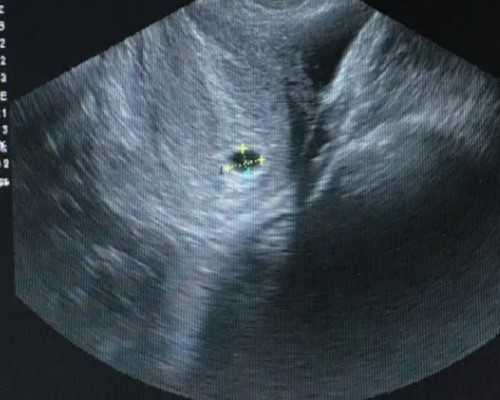

4、B超单明确符合胚芽达到10毫米或以上且孕周满7周即可,记得带上B超单,因为在抽血之前需要提供B超单才会为你进行鉴定。

通常为人们所熟悉的测胎儿的性别的方式是B超,但是B超有时候会因为胎儿的姿势、角度,还有医生的水平导致有误差,并且运用B超技术确定胎儿性别所需的孕周较长。

B超和验血不同之处在于,B超要等到胎儿足够大时才能观察,而且存在翻盘的可能,DNA验血最早在怀孕6个星期以上可进行,1-2个工作日出结果。这种检查手段在受孕后7周以上便可执行,而且准确率比B超高,达到99.9%。

1、首先,宝妈一定要确保孕期达到了7周或者7周以上,并且在当地的医院检测出胚芽的长度达到10mm或者10mm以上。

2.B超确认怀孕是否达到45天以上,目前也是香港最快的验血周期了,之前都是七周,也就是49天,随着技术的进步,提前了4天,B超也可以在当地做,带过来即可,也可以过来做,看个人选择,主要是过来做肯定麻烦一点。所以最好在当地做。

1、怀孕满7周 ,B超承认胚芽有10MM.有胎心搏动.

稍微了解的人都会知道,香港验血查男孩女孩是目前最流行最安全也是准确度比较高的一种查胎儿男女的方式,准确率是达到99.8%以上。只要B超确认怀孕满6周或以上,胚芽数据达到3mm或以上就可以做这个检测.

通过B超才可以准确知道孕妈的孕周是否达到7周或者以上,胚芽长度是否大于9MM。

香港验血查男女需要提供B超单的原因除了确保孕周跟胚芽长度达到要求之外,还需要确保胎儿发育正常,如是否有胎心、是否停胎、孕囊的位置是否为宫内等。

如果七周后的胎儿没有胎心、或者宫外孕、又或者已停胎,那么这个时候去香港验血查宝宝男女已没有任何意义,也会让准妈妈们徒增伤感,所以在去香港验血查男女前需要确保胎儿发育是否健康。

同样,为确保达到符合检测的要求,也为了确保孕周的准确性。确认孕周期需要依靠医学手段来进行计算,而B超确认孕周期最为准确的。